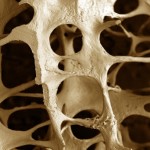

Ellos encontraron que los roedores alimentados con una forma farmacéutica de la hormona durante un período de dos semanas perdió 78 por ciento de su hueso esponjoso. Los ratones diseñados para producir el exceso de FGF21 tenido efectos similares. Por el contrario, los investigadores descubrieron que los ratones que carecen por completo de la hormona tuvieron ganancias similares en la masa ósea.

Mientras que los efectos de sensibilización a la insulina de FGF21 hacen ser un potente medicamento contra la obesidad, que podría ser anulada por riesgo de osteoporosis y fracturas asociadas con la pérdida de masa ósea, informaron los investigadores.